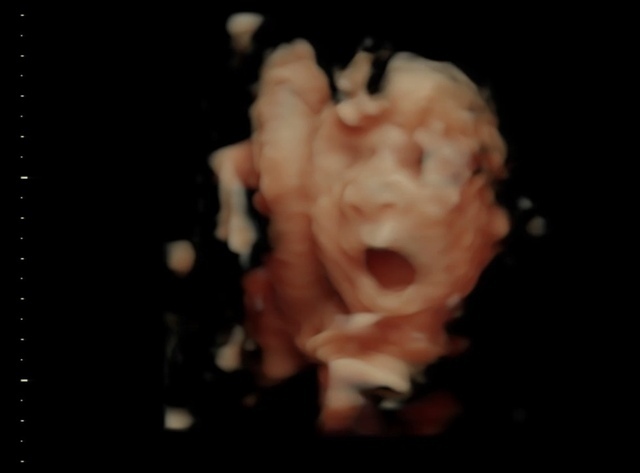

27週0日(27w0d・女の子)|いせりんご さん(25歳)

エコー写真撮影時のエピソード:

はじめての4Dエコーではっきりお顔が見えました!お腹の中であくびをしていてとっても気持ち良さそうなのが印象的です(笑)のびたり寝たり口を動かしたりと元気そうな様子でした!昨年11月に出産しましたがエコーの顔と全く同じ顔だったのでびっくりしました!あの頃と同じで今もスヤスヤよく寝る子です!